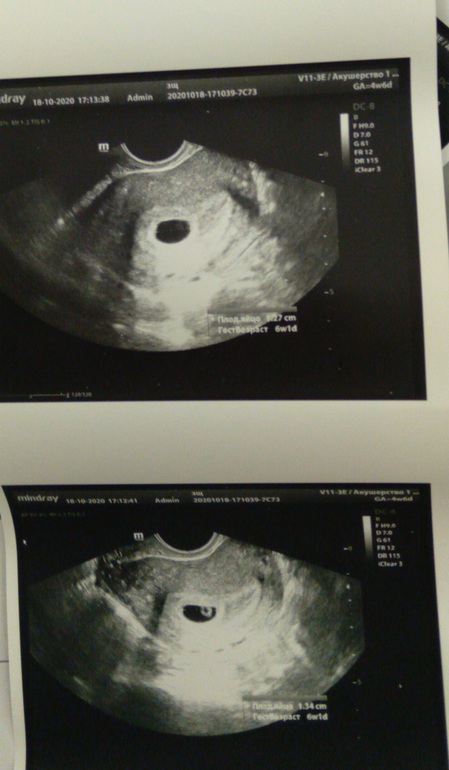

Первое узи моей малютки)

Забеременела в начале месячных, точнее за несколько часов перед ними, такое возможно? У кого так было? Нам 6 недель. Люблю тебя маленький мой